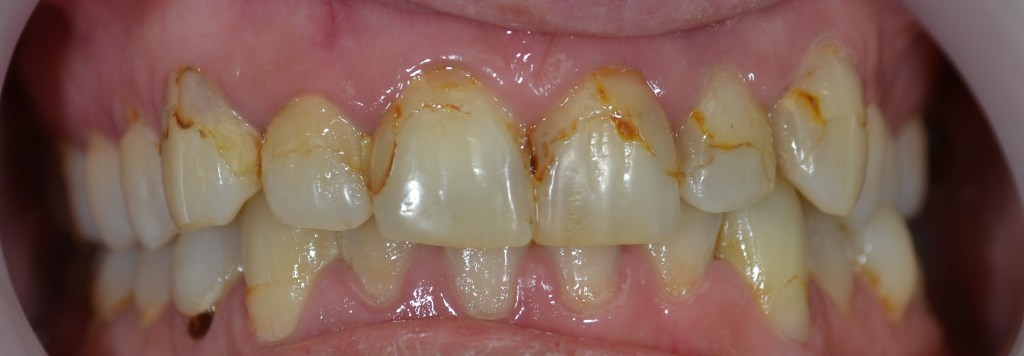

Kozmetikai és funkcionális kezelés: a kopott, elszuvasodott fogak szanálásával, hiányzó frontfogak híddal történő pótlásával, harapás megemelésével.

A választott korona típusa: CAD/CAM (komputer vezérelt tervezés/megmunkálás) technológiával készült cirkónium (fémmentes) szóló koronák, front híd.

A választott fogszín: BL 3 .

A protetikai munka elkészülésének ideje: 10 munkanap.